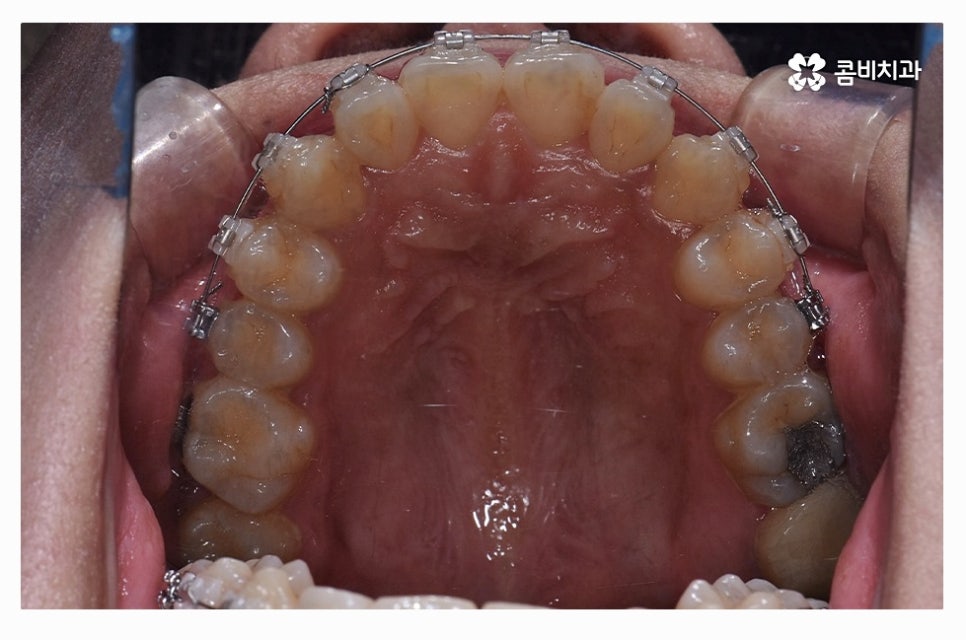

치아교정은 장기간의 치료 계획을 세워야 하기 때문에

교정 효율성이 좋고, 상대적으로 통증이 적으며 관리가 편리한

클리피씨 장치가 보편적으로 많이 활용되고 있으며

치열 상태나 환자의 니즈에 따라서 심미성이 높은 설측교정이나

투명교정이 활용되는 경우도 있어요.